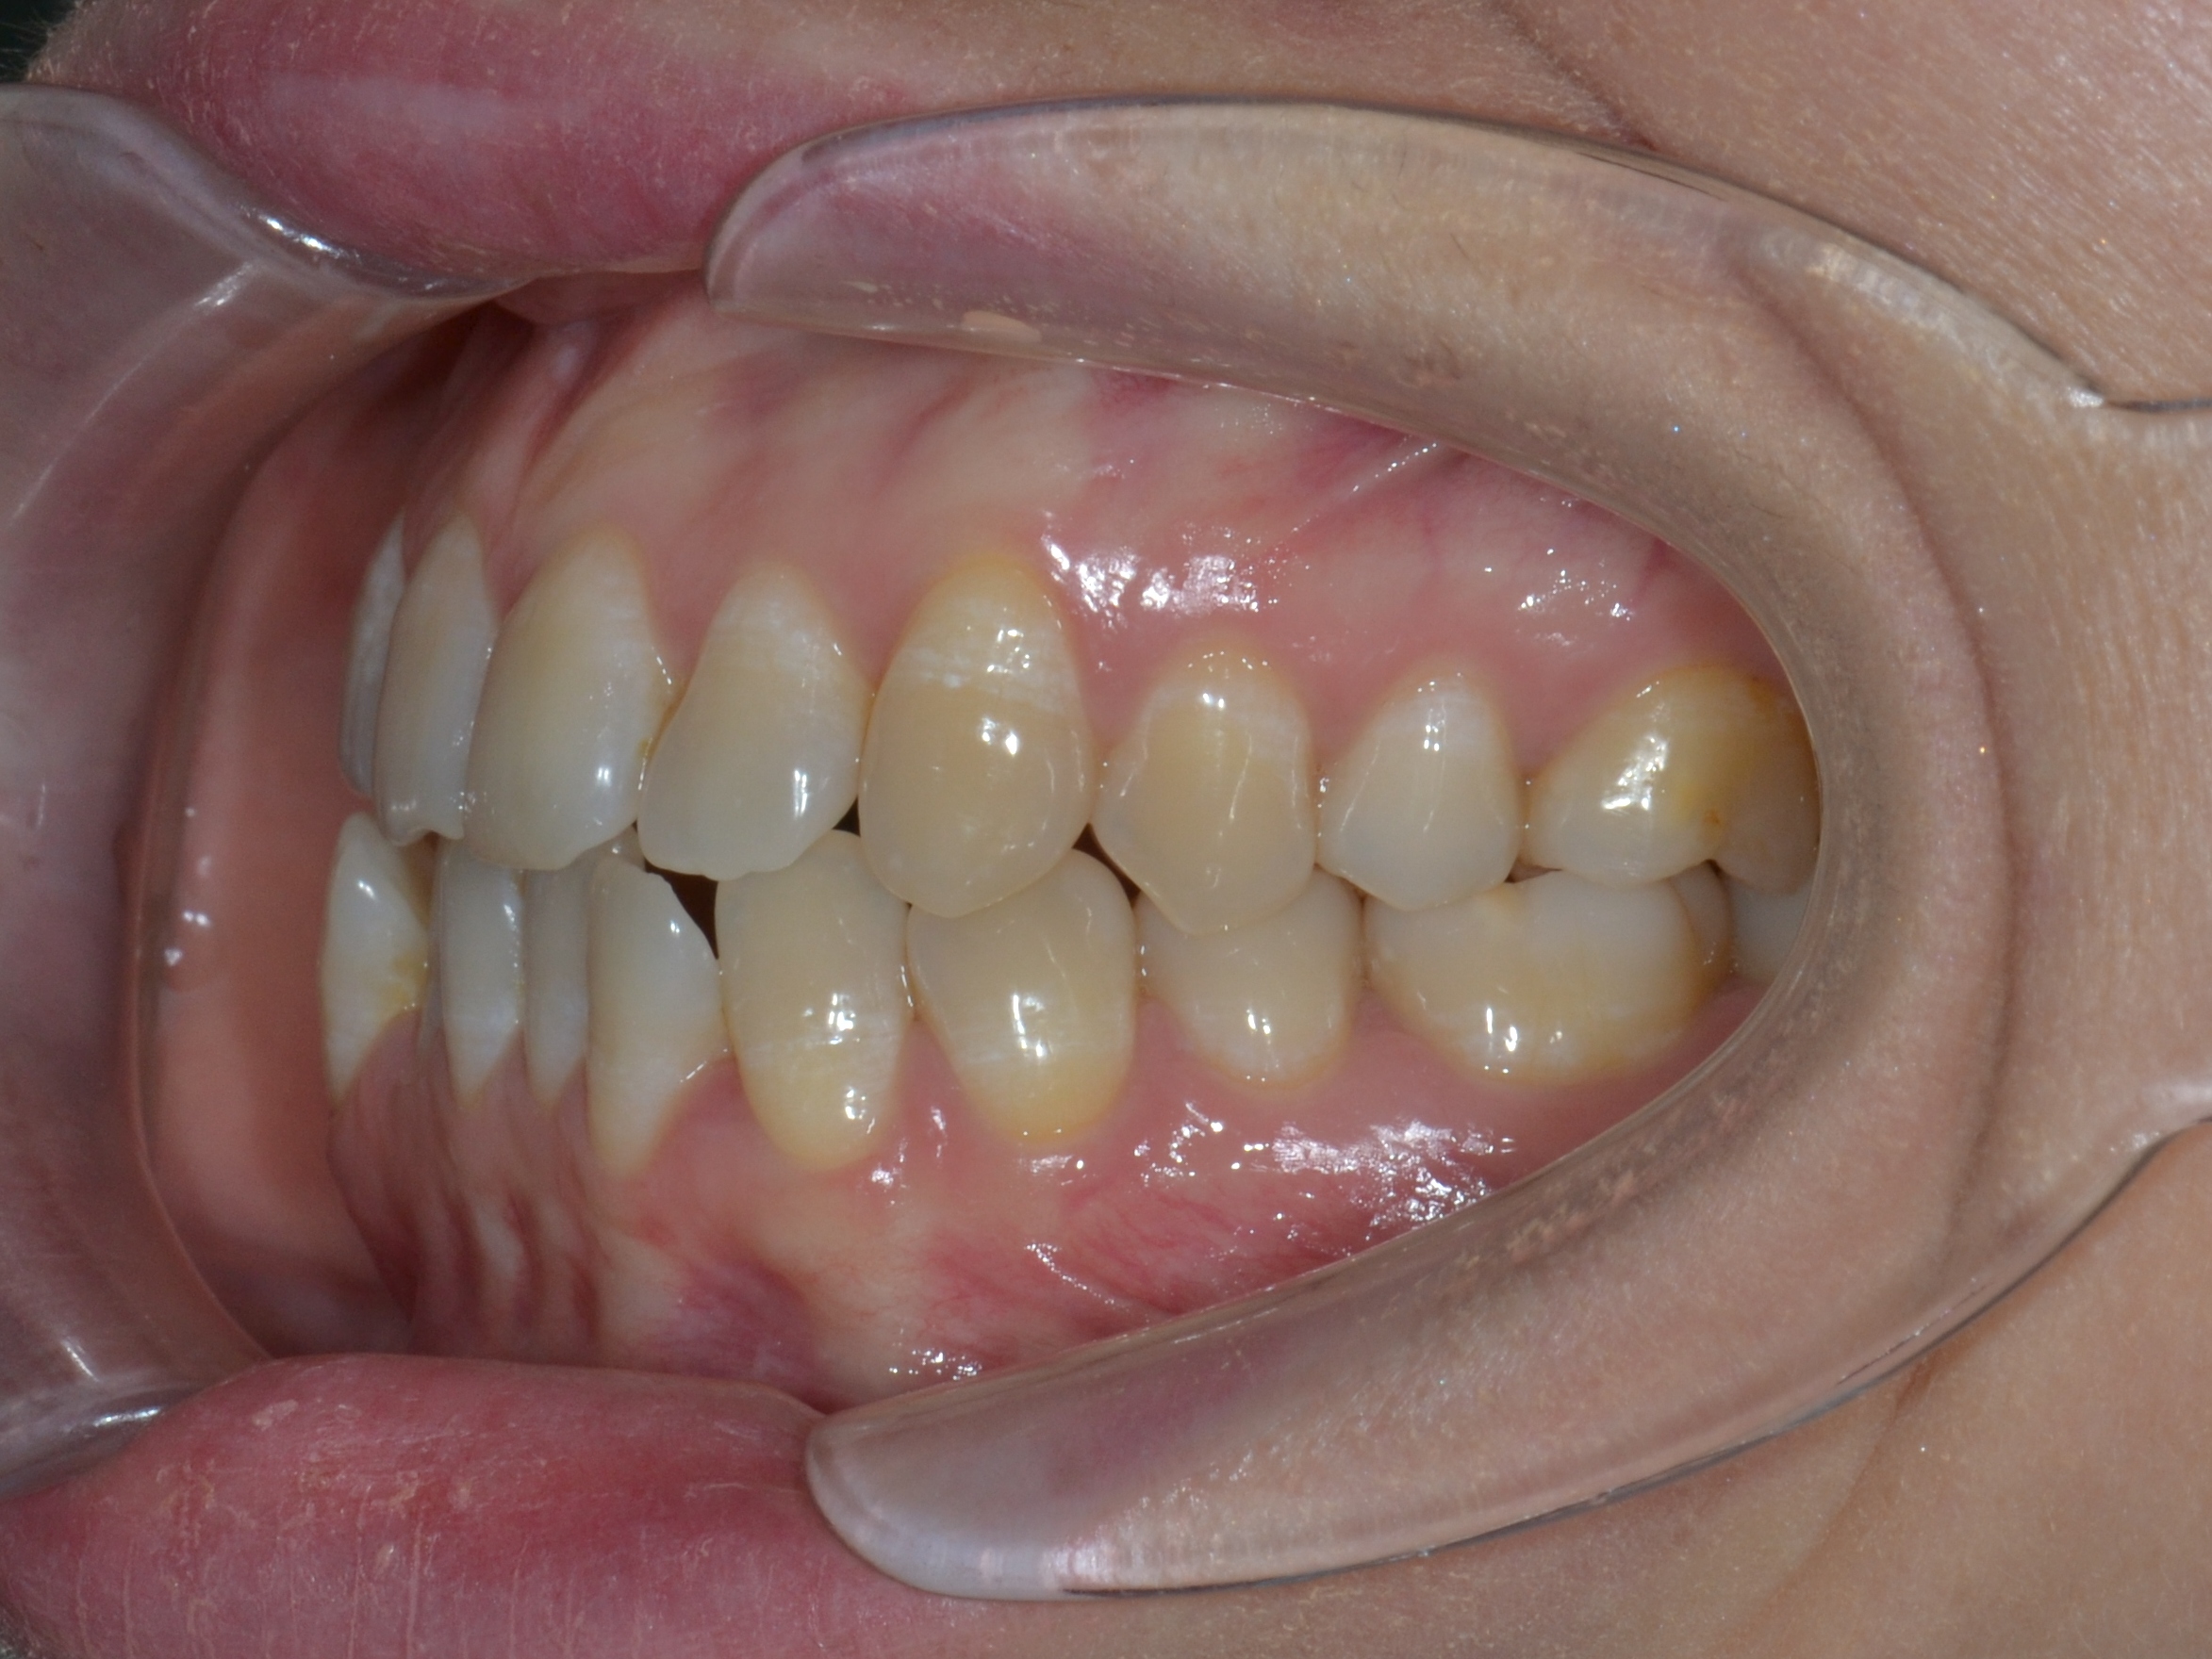

Выявленные проблемы

• Дистальная окклюзия

• Дефицит апикального базиса

• Сужение зубных рядов

• Вестибулярное положение клыков

• Скученность во фронтальных и боковых отделах

Брекет-система Pro